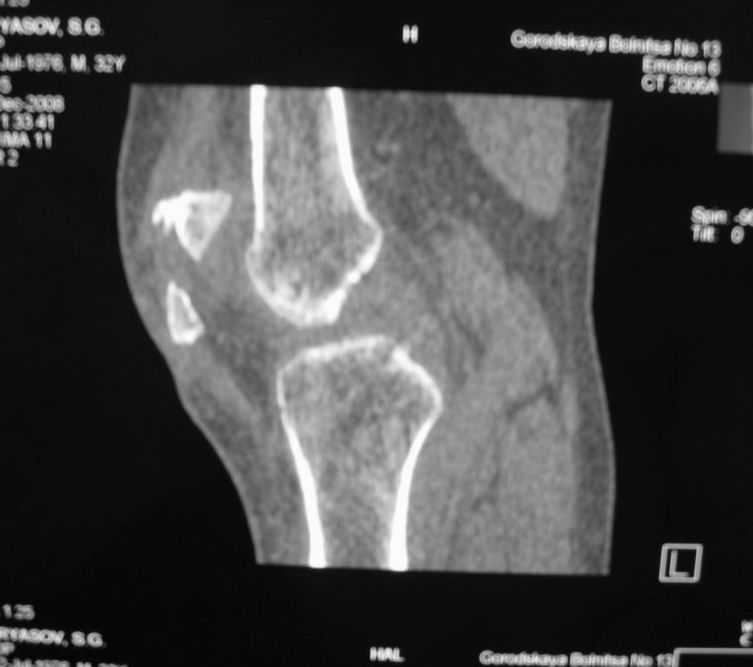

Уважаемые коллеги! Обратился пациент 32 лет с травмой коленного сустава от июля 2008 года - падение с мотоцикла, прямой удар передней поверхностью коленного сустава. Диагноз - открытый оскольчатый перелом надколенника. В одной из больниц города выполнили ПХО, шов надколенника лавсаном. Заживление раны с частичным нагноением(разведена на участке 3 см).Сейчас мягкие ткани в порядке. R-снимки, КТ в приложении. Объем движений 0/0/110 гр.Ходит почти без хромоты. Жалобы на торчащий под кожей один из отломков, боль в этой точке. Вопрос: что делать? Первое - убрать этот отломок и на этом закончить. Второе - оставить все как есть(отломок не так уж и сильно мешает). Ждать возможного развития артроза, дальше по ситуации. Третье - подумать о протезировании надколенника.

Внешний вид коленного сустава